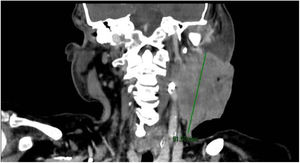

Varón de 64 años, fumador activo que acude a urgencias por presentar una tumoración cervical izquierda junto con fiebre elevada y malestar general de varios días de evolución. A la exploración física: tumoración de 7×4cm con supuración activa y pétrea a la palpación (fig. 1). TAC de tórax y cervical urgente: gran masa de partes blandas, laterocervical izquierda, con densidad heterogénea y burbujas en su interior (fig. 2), invadiendo planos grasos profundos y fistulizando al exterior 8×9cm (fig. 3) compatible con masa maligna abscesificada. Ingreso en la UCI por shock séptico para recibir tratamiento intensivo. Diagnóstico definitivo: neoplasia de la base de la lengua con adenopatía metastásica abscesificada.